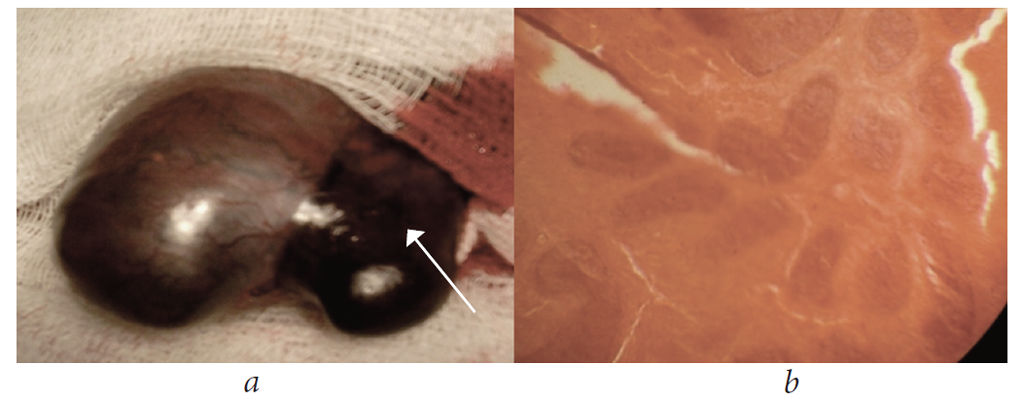

During scrotal exploration, the color of tunica was evaluated, the tunica vaginalis was opened, and transudate was evacuated. Then, the testicle was untwisted (open detorsion was performed) and its viability and the presence of signs of necrosis were evaluated. In patients with cherry-colored, viable testicle with signs of incomplete torsion of 180° and time of onset ≤ 6 h, the testicle was rotated in the direction opposite to the median septum of the scrotum (from the inside outward); that is, the right testicle was rotated clockwise and the left testicle counterclockwise. After torsion was released, the testicle color was evaluated, and for 10–15 min, they were covered with napkins abundantly moistened with warm saline. Excess tissue of the tunica vaginalis was dissected and coagulated. To prevent hydrocele development, the edges of the tunica vaginalis were rotated and fixed with 2–3 sutures using a 3/0 synthetic absorbable suture. Subsequently, the testicle was fixed to the median septum of the scrotum in the tunica albuginea or tunica dartos. For complete testicular torsion (360–540°) and testicular necrosis, orchiepididymectomy was performed. A drainage tube was inserted into the wound. To prevent inflammation and destructive changes, antibiotics were administrated. The histological study of the specimen revealed hemorrhagic infarction of the testicle (Fig. 6).

Fig. 6. Patient, 31 years old, gross specimen (necrotized testicle), 360° torsion, received non-surgical treatment for 2 days before hospitalization (a); hemorrhagic infarction was verified morphologically (b)